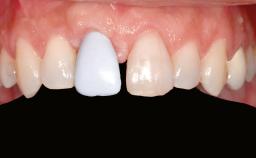

Ridge Preservation and Implant Placement for a Fixed Dental Prosthesis After a Car Accident

It is well known to clinicians that any removal of teeth will, over time, cause the dimensions of the alveolar ridge to be reduced by resorption of the bundle bone and by changes related to external modeling. This development is particularly evident in the crestal region with its thin buccal bone that consists of bundle bone almost entirely. The facial bone will rapidly resorb as blood supply from the periodontal ligament gets disrupted (Araújo and Lindhe 2005). There is no reason why traumatic tooth loss should not have the same consequences. It takes more than achieving implant osseointegration for a treatment outcome to be considered successful. No deficiency of bone or soft tissue is acceptable when an ideal esthetic outcome is the goal. Several articles (Sanz and coworkers 2011; Vignoletti and coworkers 2011) have reported on techniques of improving the alveolar ridge for implant treatment, notably focusing on protecting tissues from resorption.

Prosthesis Type FDP

Soft Tissue Anatomy Intact Defective

Bone Volume Horizontally and vertically sufficient Horizontally deficient Deficient vertically or deficient vertically AND horizontally